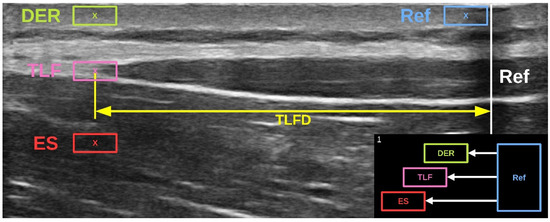

The investigator, who was blinded to the group membership, measured the TLFD sonographically from each participant as described in Section 2.1. A US video of the entire trunk extension task was then recorded from the TLF (for more details on this procedure, see Brandl et al. [23]). The videos were then tracked in post-analysis using Kinovea (version 0.9.5; Kinovea open source project, www.kinovea.org). The tracking pixels from the videos were tested for several scenarios, and Kinovea was recommended as a valid and reliable tool [31,32]. The individual speckle tracking of pixels was applied within a 4 × 7 mm rectangle representing the region of interest as described by Rodriguez et al. [33]. The analysis involved the determination of lateral tissue displacement from the starting to the ending position (Figure 1). The measured pixels were converted to millimeters using the scale bar in the US video and the Kinovea calibration function [31]. The procedure was performed simultaneously by the program for the different lumbar tissue layers (dermis, SAT, TLF, and erector spinae) and the artificial reference in the US video that we had previously defined (Figure 4).

Figure 4. The speckle tracking analysis of lumbar tissue. The respective pixels of the regions of interest (4 × 7 mm rectangles) are tracked in an ultrasound video showing the trunk extension task. The displacement of DER, TLF, and ES from the Ref was post-analyzed using Kinovea software, version 0.9.5. Ref, artificial reference of reflective tape on the skin; DER, dermis; TLF, thoracolumbar fascia; ES, erector spinae muscle; TLFD, deformation of the TLF.